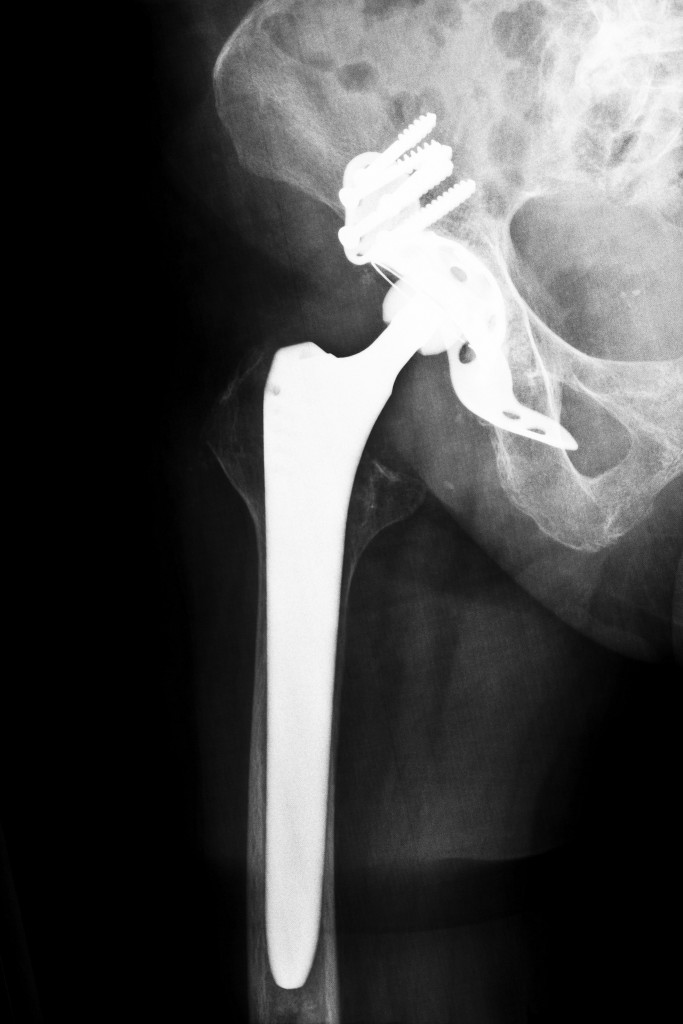

Hip joint replacement xray showing ball and socket joint's titanium Hip Ball Replacement Video A new version of this animation is now available! I'm an orthopedic surgeon and we're about to perform a total hip replacement for a patient. The procedure is also called hip hemiarthroplasty. This animation explains total hip replacement, a surgical procedure in which parts of an arthritic or damaged hip joint are removed and replaced. Anterior total hip replacement surgery,. Hip Ball Replacement Video.